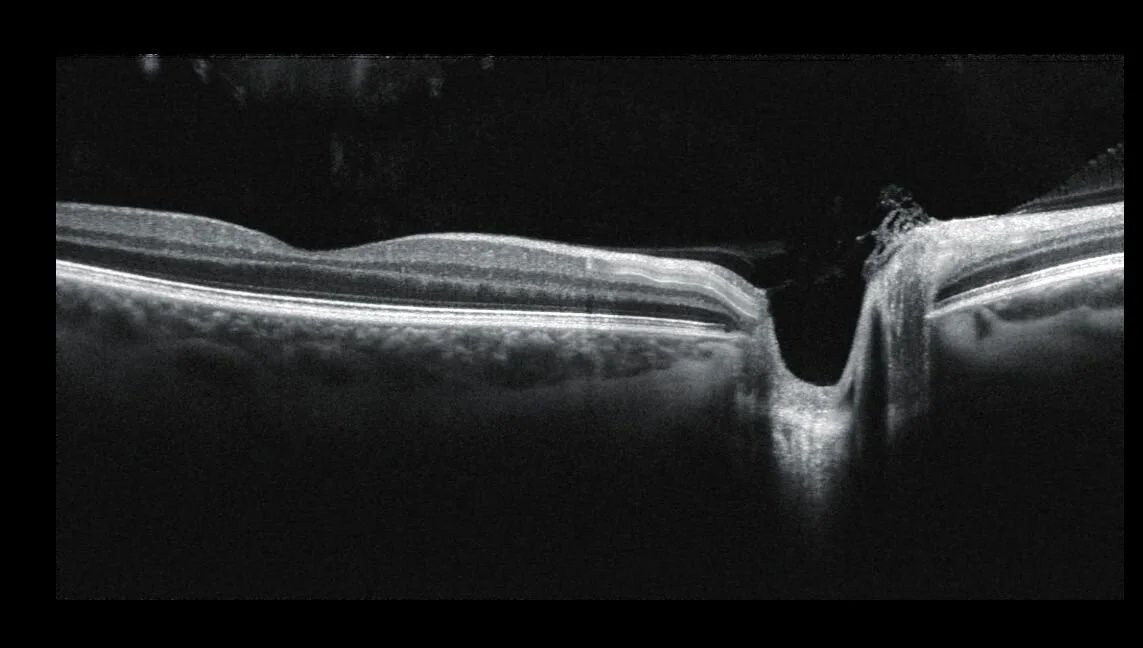

OCT

3D Optical Coherence Tomography is a completely painless and highly advanced eye scan for people of all ages, which can identify a number of common and potentially serious conditions. We are among a growing number of professional optometrists who provide this service.